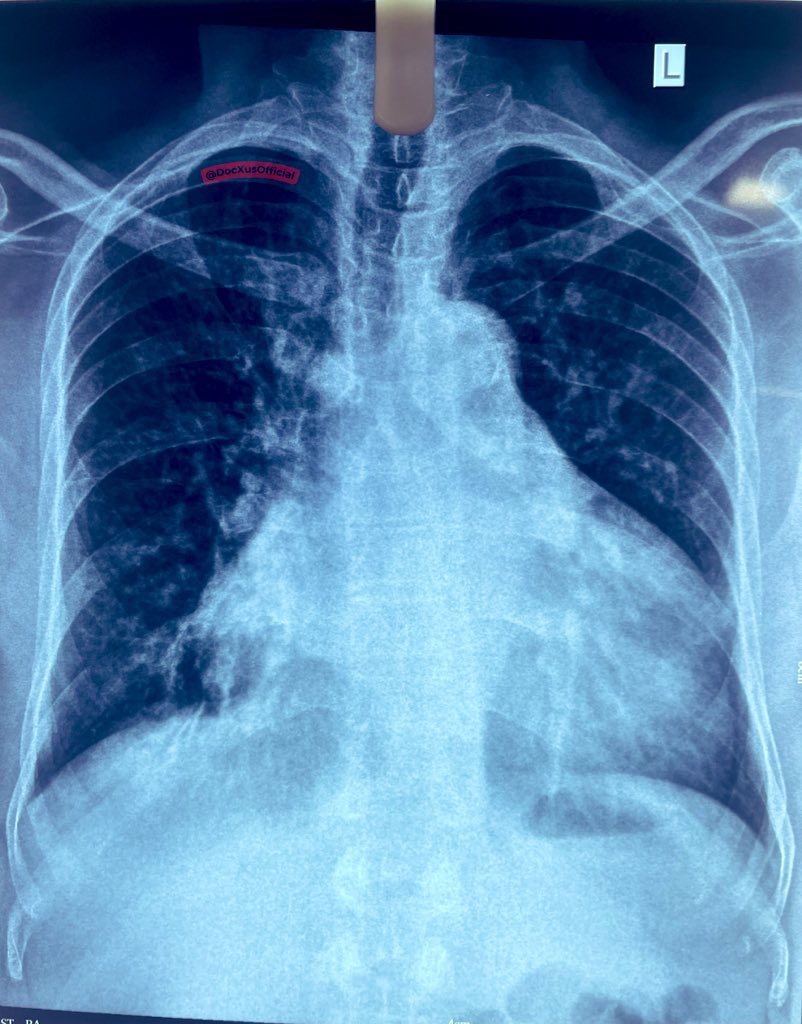

A 24 year old was brought to the ER with a heart rate of 212

HR 212 on the monitor. Narrow complex tachycardia